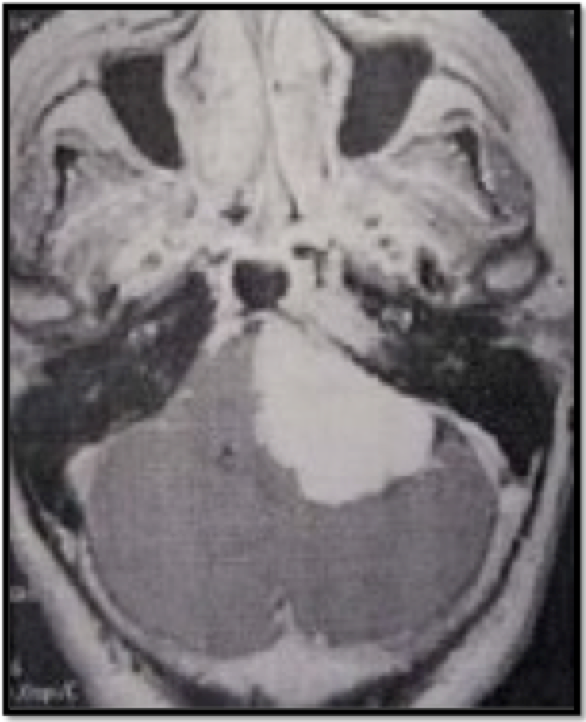

Perhatikan Gambar di bawah ini. Diagnosis manakah yang paling mungkin?

A. Sklerosis tuberus

B. Pakigiria

C. Invaginasi basilar

D. Malformasi Chiari I

E. Malformasi Chiari II

D